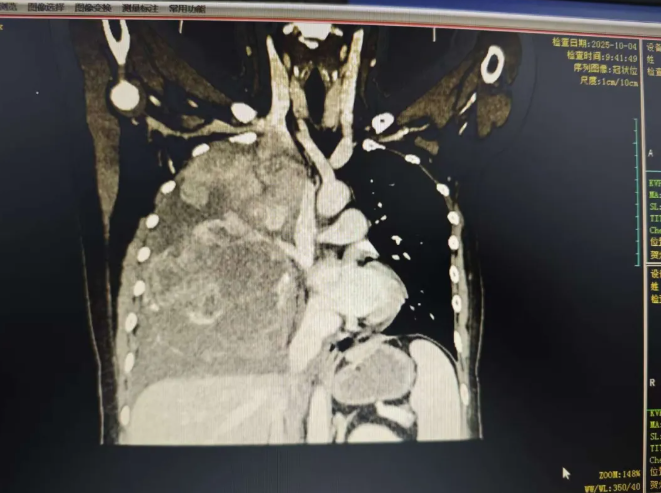

这位27岁的年轻女孩,最近几个月一直被反复的胸闷、咳嗽和气短所困扰。来到贺州市中医医院检查后,结果让人大吃一惊——她的右侧胸腔内,长了一个巨大的肿瘤。

这个“不速之客”体积惊人,长约30多厘米,几乎占据了整个右侧胸腔,将患侧的胸廓都撑大了,并导致右肺受压、体积缩小,还伴有胸腔积液。巨大的肿瘤压迫让她感觉 “连呼吸都成了负担”。